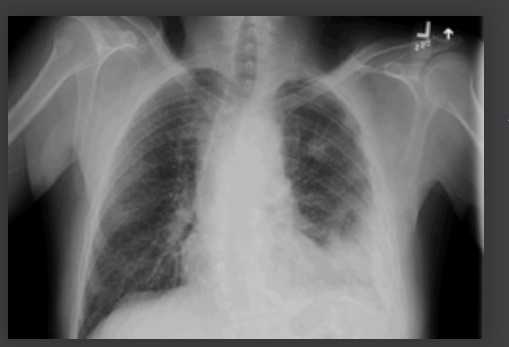

Considere uma tomografia computadorizada de tórax ou outras investigações de imagem para pneumonia “complicada” ou alterações atípicas em uma radiografia torácica, como cavitação, padrão de consolidação multifocal ou derrame pleural.[89][Figure caption and citation for the preceding image starts]: Radiografia de tórax mostrando pneumonia cavitando no lobo superior esquerdoDa coleção do Dr. Jonathan Bennett. Usado com permissão [Citation ends].

[Figure caption and citation for the preceding image starts]: Derrame pleural no lado esquerdoDa coleção do Dr. R Light. Usado com permissão [Citation ends].